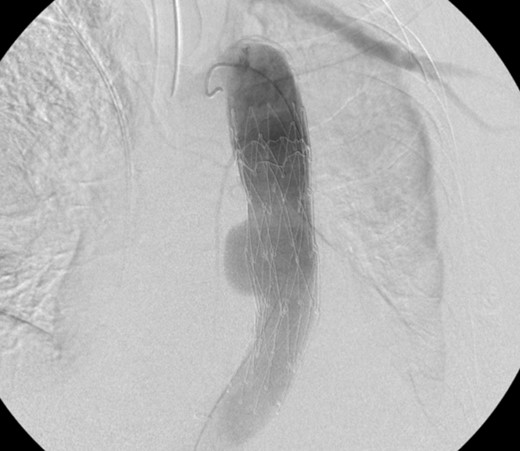

Aortogram showing successful deployment of covered stent graft.

TEVAR can be safely employed to treat an aorto-esophageal mycotic thoracic aneurysm when open repair is not possible because of patient’s comorbidity. Post-operatively our patient was asymptomatic and imaging demonstrated the stent graft in excellent position, without endoleak, and complete resolution of the aneurysm sac. Long-term follow-up is necessary for detection of endoleak, recurrence, or aneurysm propagation.